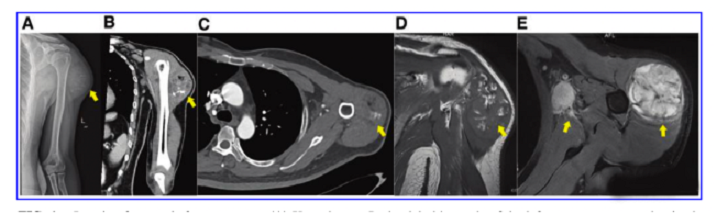

接受iPS細(xì)胞治療患者的畸胎瘤。(A) 在左上臂的三角肌中,觀察到一個圓形的混合密度腫塊,邊界不清,為9.6±5.2cm。(B) CT冠狀掃描顯示三角肌內(nèi)有一圓形混合密度腫塊,邊界不清。(C)增強(qiáng)CT軸向掃描顯示不均勻和中度強(qiáng)化。(D)MRI T1W以等信號為主,有不規(guī)則的高低信號區(qū)。(E) T2W也顯示高信號和斑片狀低信號區(qū),左腋窩有多個淋巴結(jié)腫大。

文中展示了該未成熟畸胎瘤的臨床,放射學(xué)和病理學(xué)特征,作者認(rèn)為這種腫瘤不同于典型的未成熟畸胎瘤,特點是快速增長和局部淋巴結(jié)轉(zhuǎn)移,該新生腫瘤對典型化療方案沒有反應(yīng),磁共振成像顯示腫瘤的不均勻強(qiáng)化和豐富的血供。